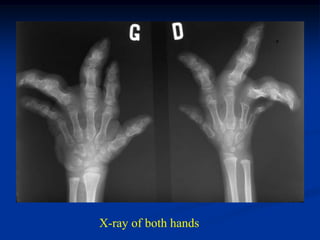

5 year female with Ollier’s of hand ready for surgery

X-ray of both hands